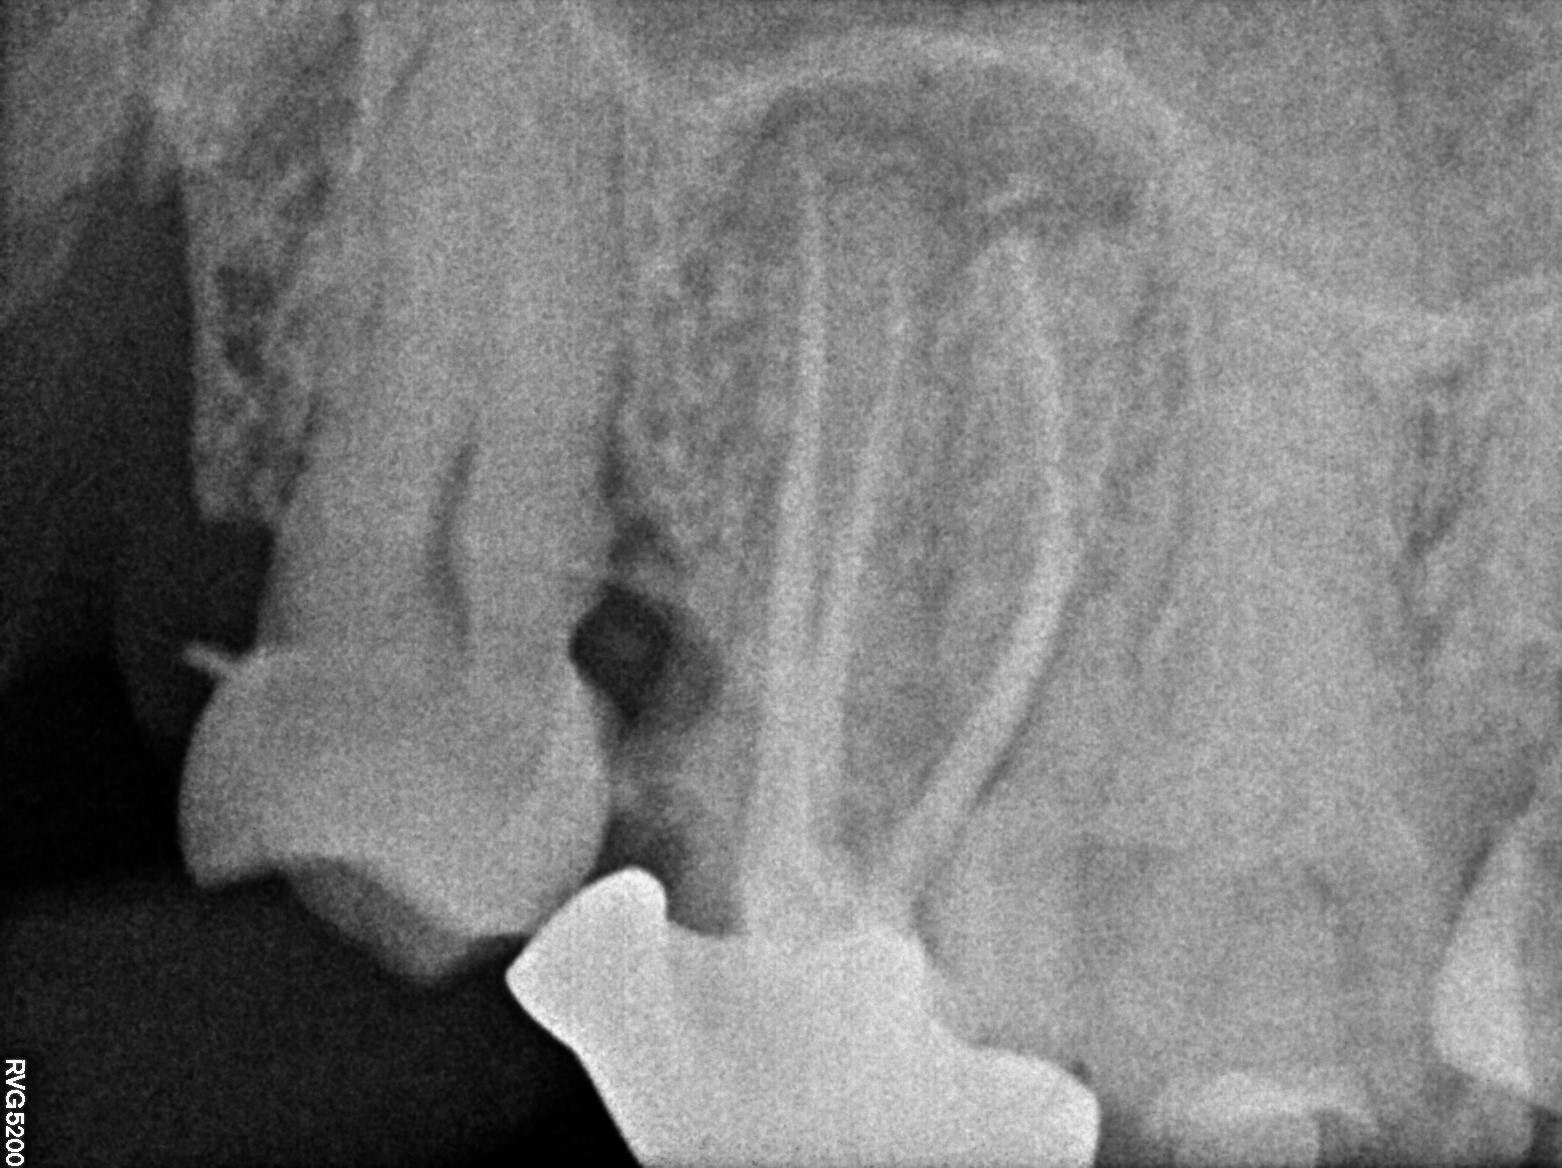

Dental Radiographs FHIR: DocumentReference · LOINC 24641-7

R54.jpg

24641-7

| Dental caries, unspecified | K02.9 | 80967001 | resolved | 2026-03-19 | class 2 composite filling with 18 for food lodgment done. he was not willing for extraction, so this provisional treatment was performed with no guarantee | |

| Dental filling | 180534004 | D2391 Resin composite - one surface, posterior | #18 | 2026-03-19 | completed | filling done | |

| Dental filling | 180534004 | D2391 Resin composite - one surface, posterior | ##18 | 2026-03-19 | completed | class 2 composite filling with 18 for food lodgment done. he was not willing for extraction, so this provisional treatment was performed with no guarantee | |